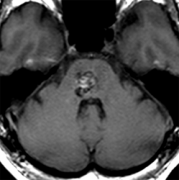

脑干海绵状血管瘤的特征和症状,和其他部位的海绵状血管瘤一样,无症状被发现的情况也很多。无症状的情况下可以观察。脑干部也有顺利区,一部分切开也不容易出症状的部分。使用两点法...

脑海绵状血管瘤无症状或者偶然发现,需要手术吗?脑海绵状血管瘤常会因非特异性或无关症状而做影像学检查时被发现(图1)。对于无症状的脑干海绵状血管瘤和单次发作并没有导致严...